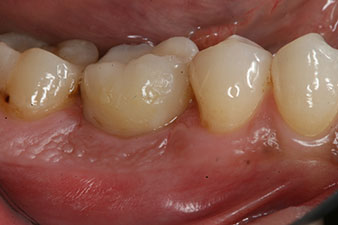

impression

Fig. 8: The impression for the final crown is taken.

Therefore, successful osseointegration and adequate biological stability could be recorded, which enabled an impression to be taken in the same session.

The final pictures show the screw-retained monolithic composite crown in place and the x-ray check (Fig. 9 and 10) (6).

composite crown

Fig. 9: The final composite crown was cemented on a PEEK hybrid abutment in the laboratory and can be screwed in place immediately.